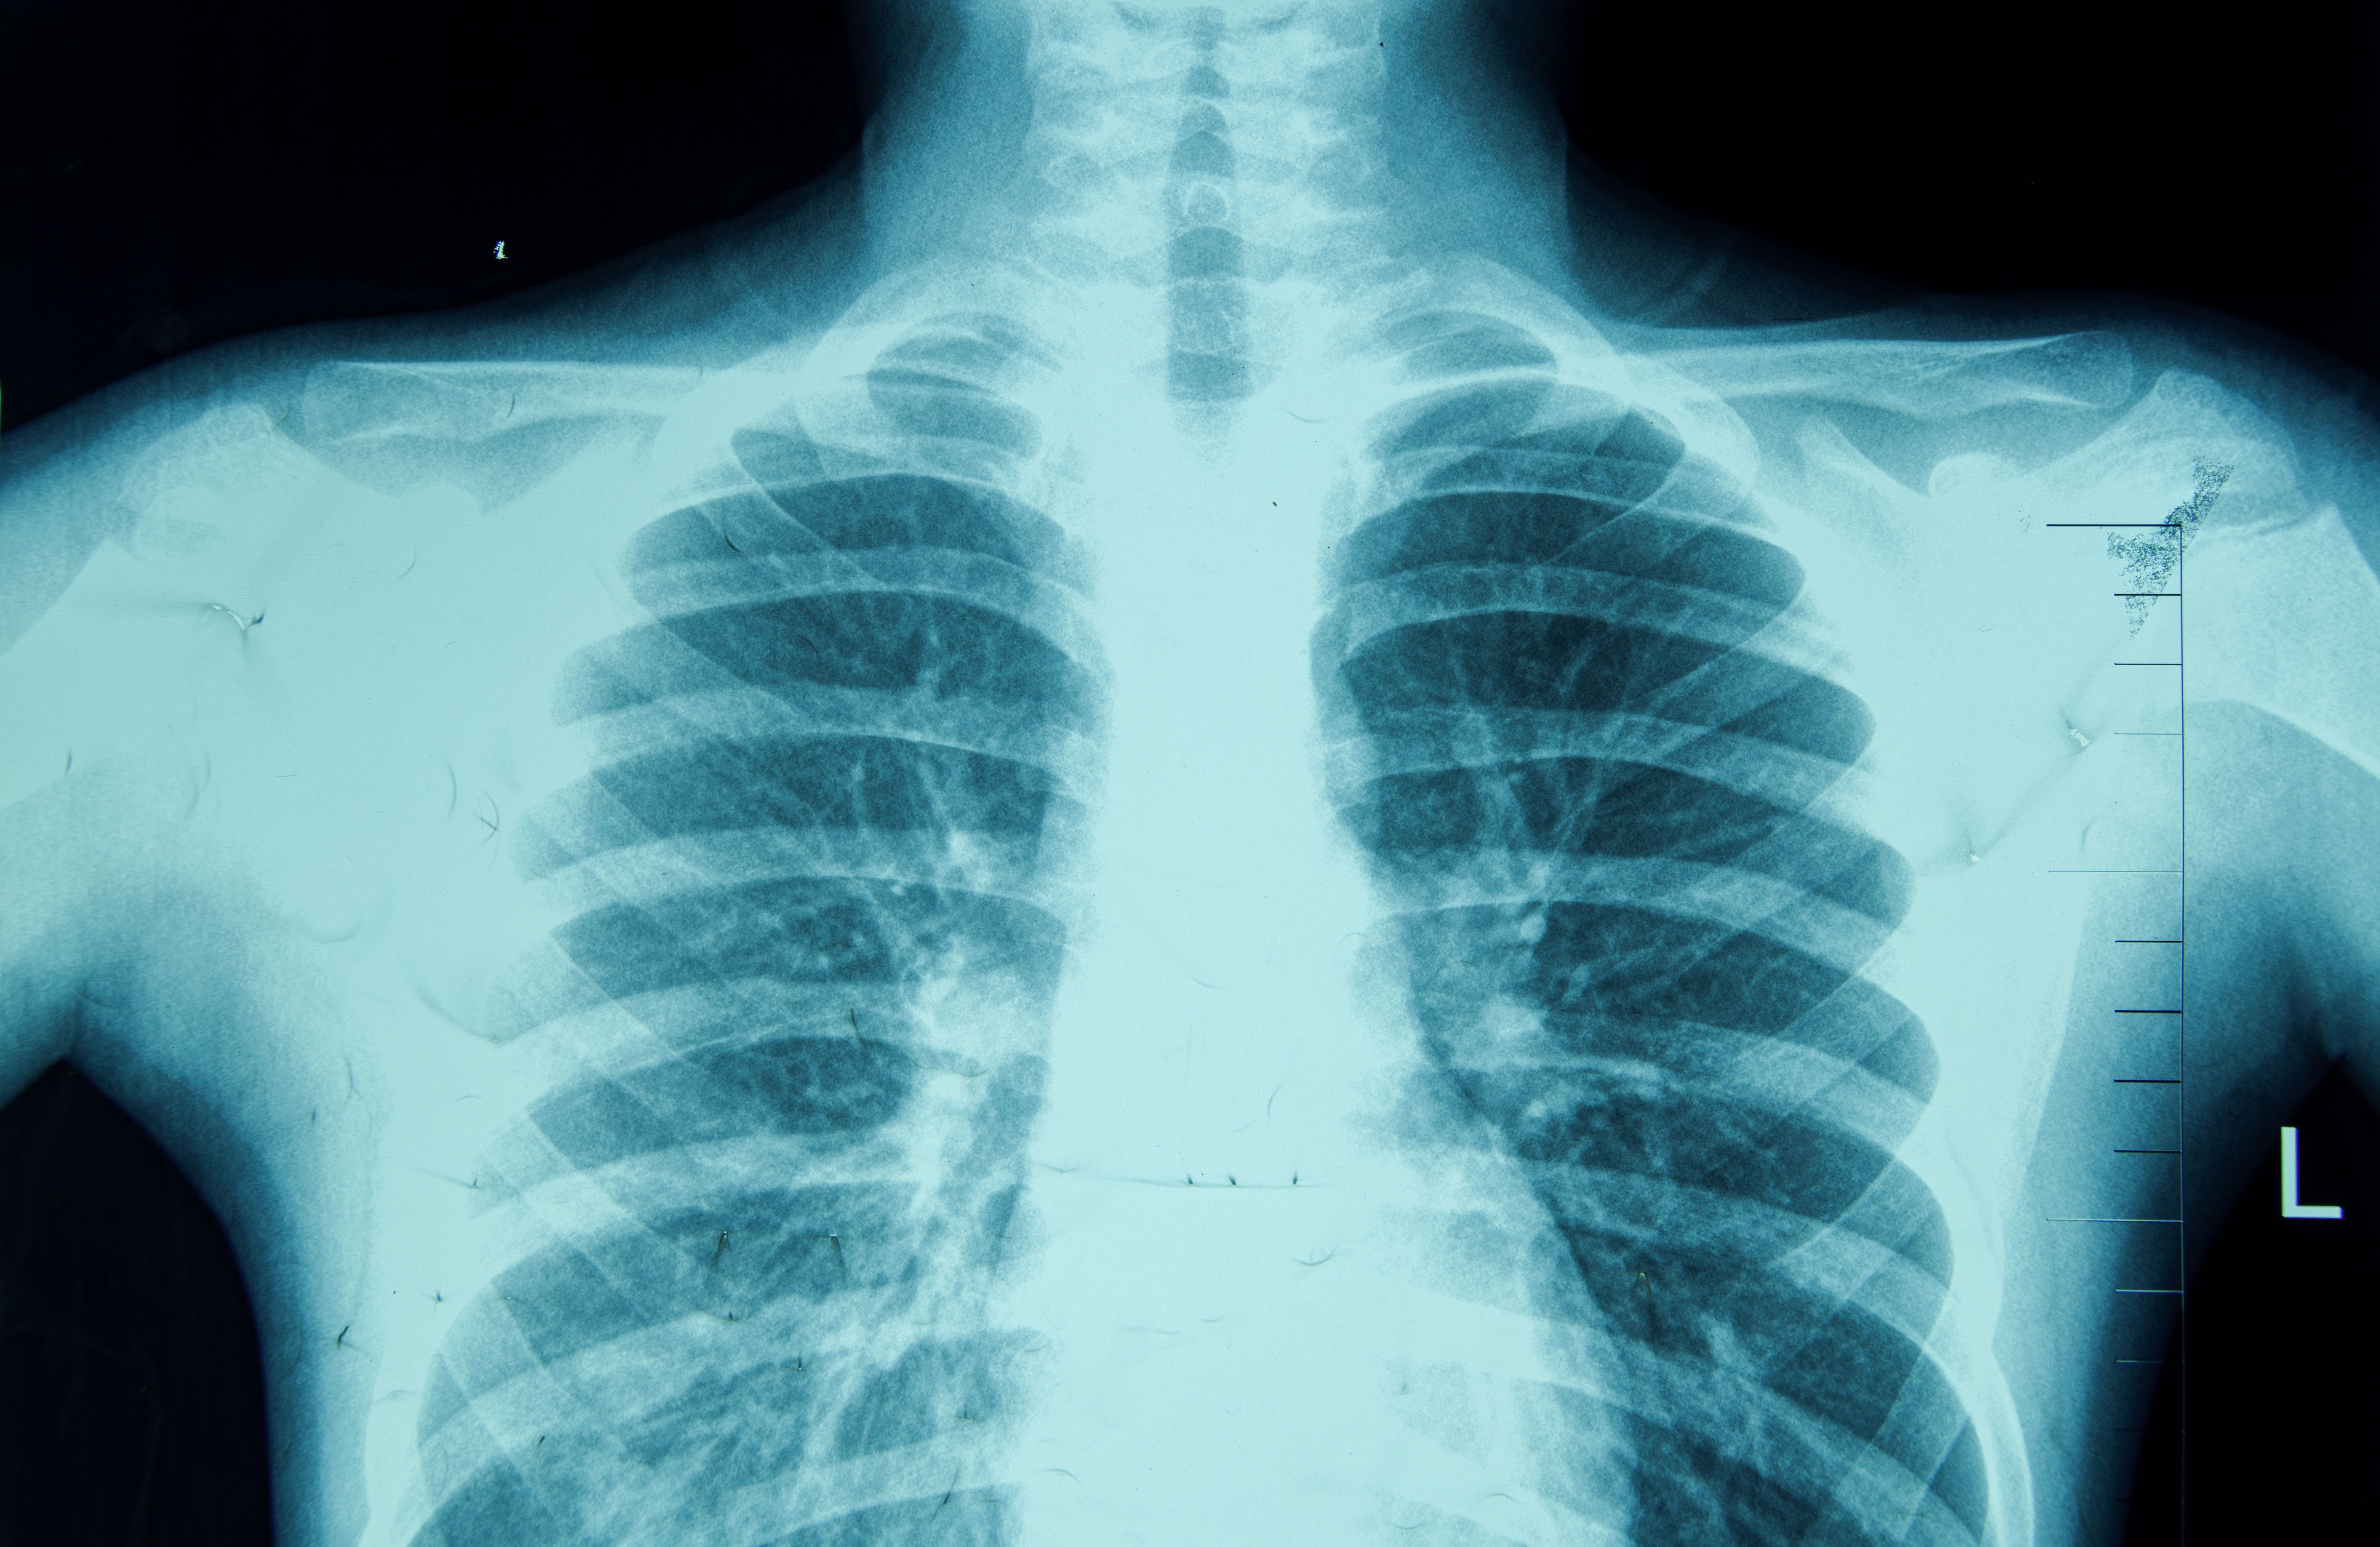

The future of OB/GYN practices is also marked by advancements in imaging technologies such as 3D and 4D ultrasounds. These tools provide clearer images of the fetus, enabling doctors to detect abnormalities at earlier stages. Enhanced imaging techniques contribute to better prenatal care and informed decision-making by both the healthcare provider and the patient.